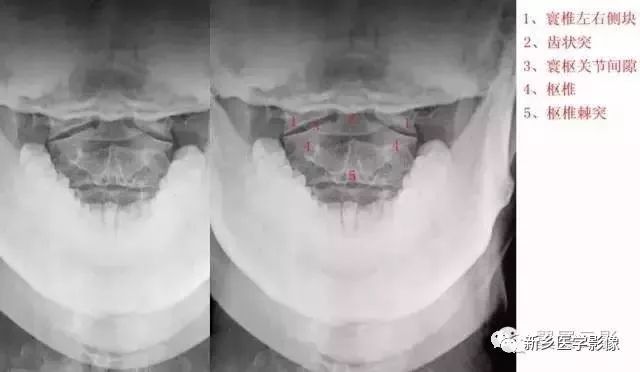

颈椎张口位

开口位片主要观察1.2颈椎有无骨折,先天缺如及环枢关节有无脱位及半脱位等情况,环枢关节半脱位一般会引起头晕,头痛,耳鸣,眼涨,等症状,临床上碰到有以上症状的,一般加拍颈椎开口位片。

十张口:指观察张口位投照的X线正位片。

(1)观察寰枢椎(2)看齿状突(3)观察寰椎椎弓(4)寰齿关节间隙

上位颈椎X光片,张口位

1 枢椎之齿突,2 寰枢之外侧块,3 寰枢关节,4 枢椎之椎体,5 第3颈椎